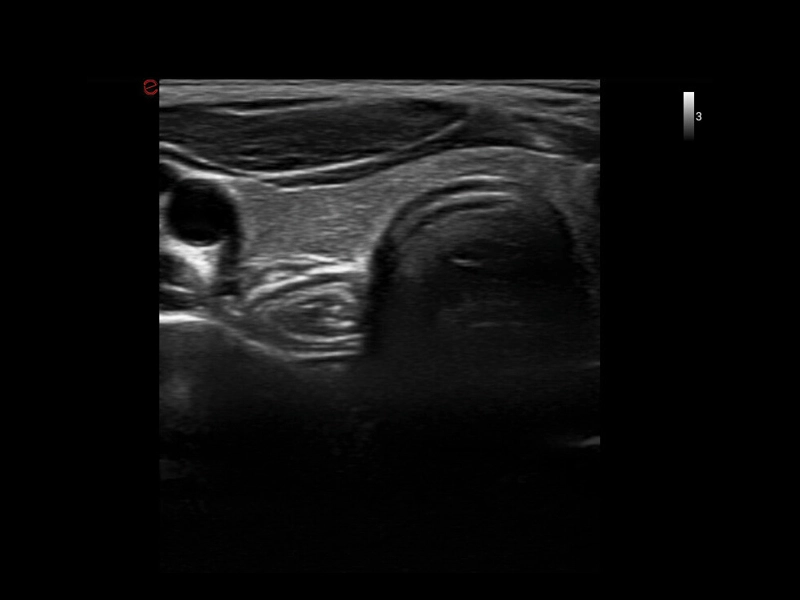

MyLab™9 Platform - High resolution imaging in testis

MyLab™9 Platform - High resolution imaging in testis